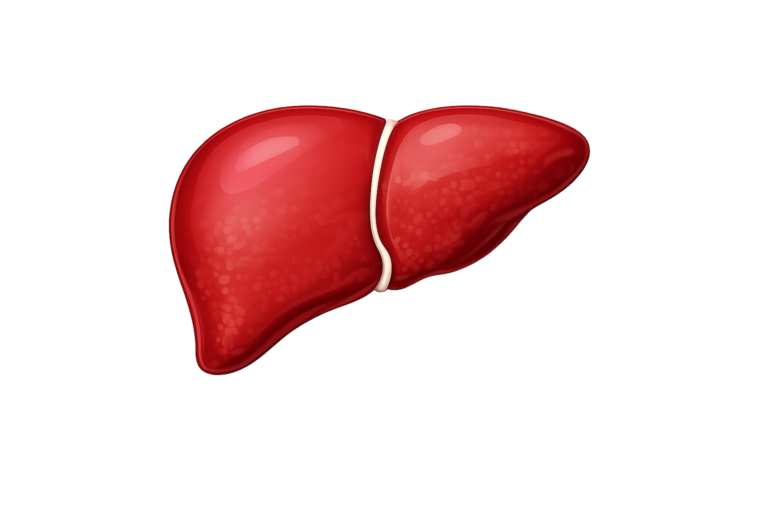

Healthy Liver

Healthy Liver